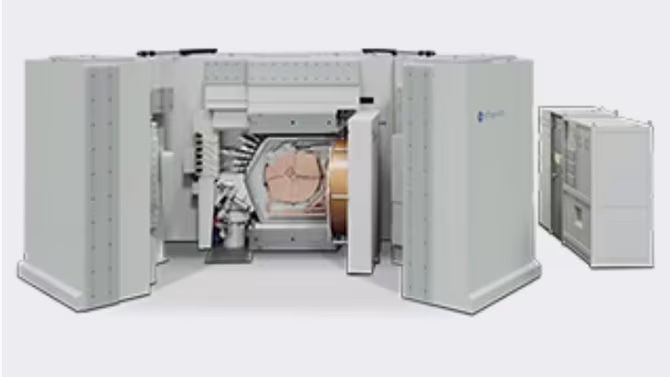

Open future

Fully upgradeable to the latest technology, applications and coils